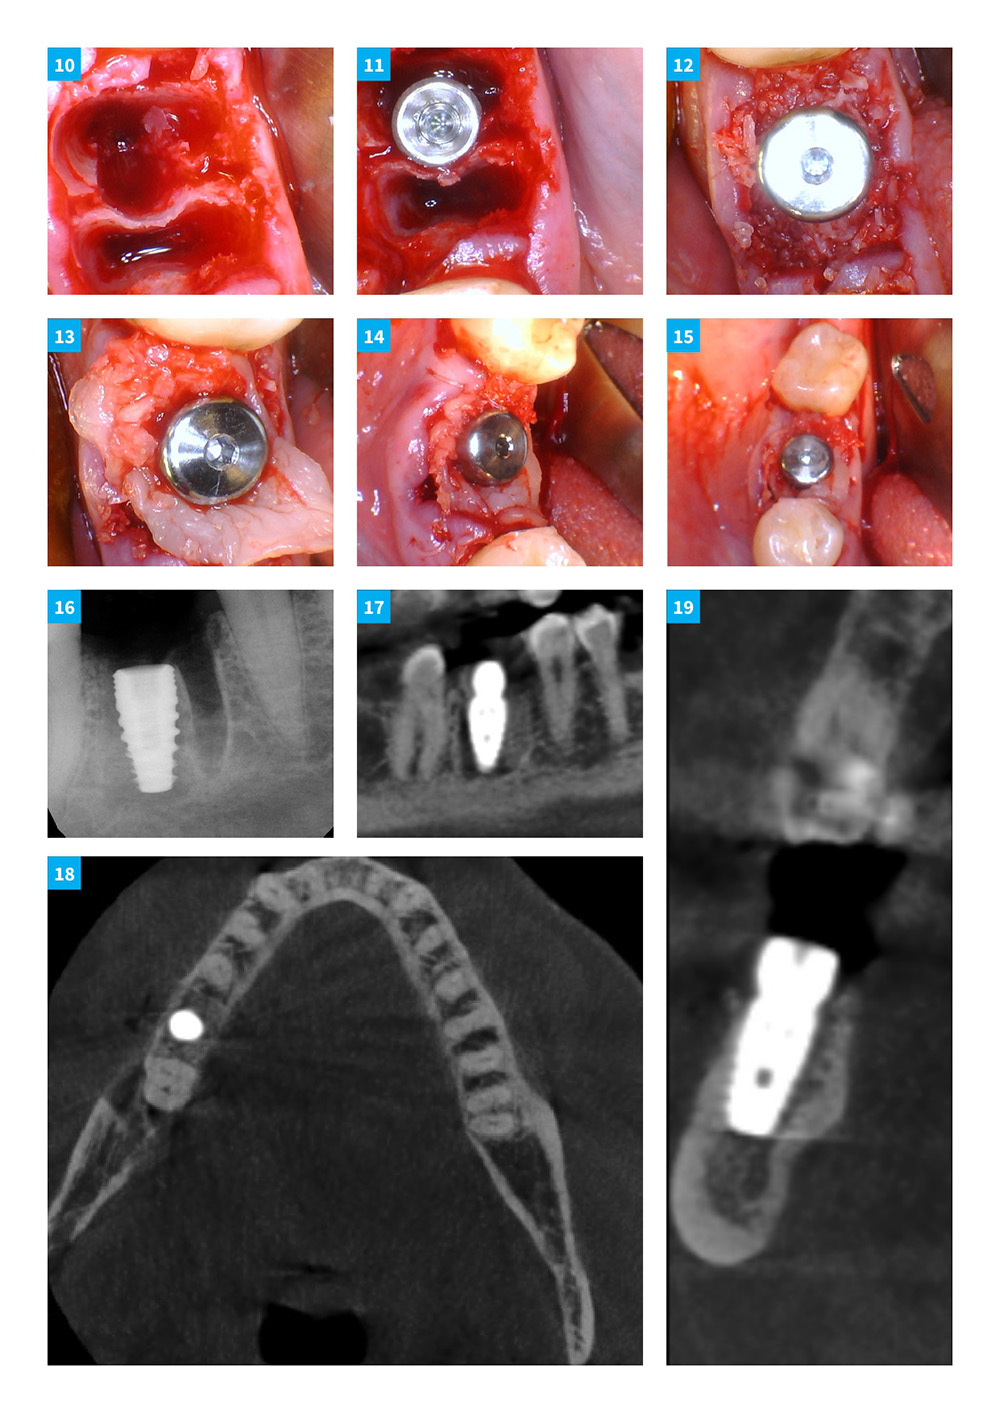

Dental Implant Continuum with DSI implants and products. Case 9